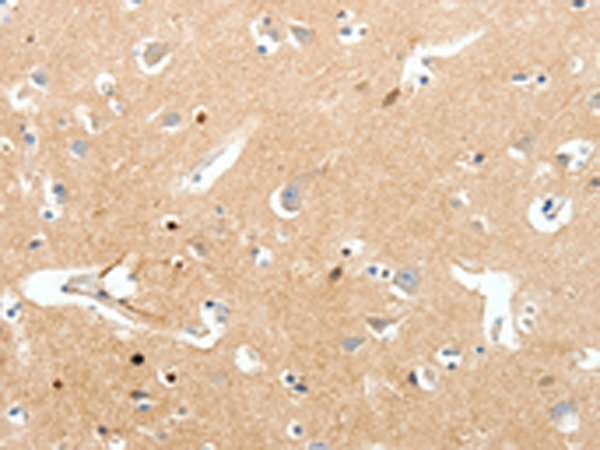

分类: 科研抗体货号: P11338别名: NaN; SNS-2; NAV1.9; SCN12A应用: IHC反应种属: Human, Mouse, Rat